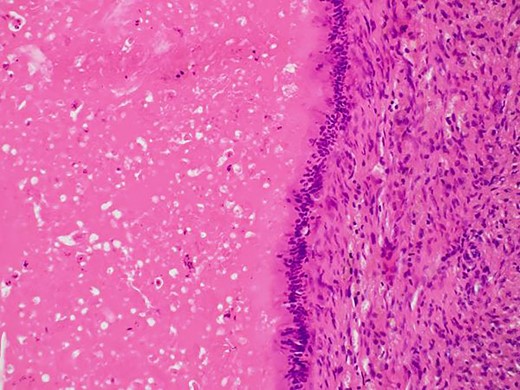

In the present case, the tumor on the patient’s abdominal wall was a lesion continuous from the deep to superficial layers of the abdominal wall. Based on immunostaining results, we diagnosed the patient with intestinal-type adenocarcinoma. Hiramatsu et al. [4] stated that when cancer and ectopic tissue coexist, identifying the transition zone between them is critical in determining the origin of the cancer. In this patient, non-neoplastic epithelial cells were present adjacent to neoplastic epithelial cells (Fig. 7a–c). These non-neoplastic epithelial cells were CDX2/CK20 positive and CK7 negative, indicating that the tumor comprised ectopic tissue of intestinal origin.

Non-neoplastic epithelial cells were present adjacent to neoplastic epithelial cells.

Differentiated ductal adenocarcinoma grew irregularly in a gourd-like pattern at the tumor area.

Non-neoplastic intestinal epithelium remained at the normal tissue area.